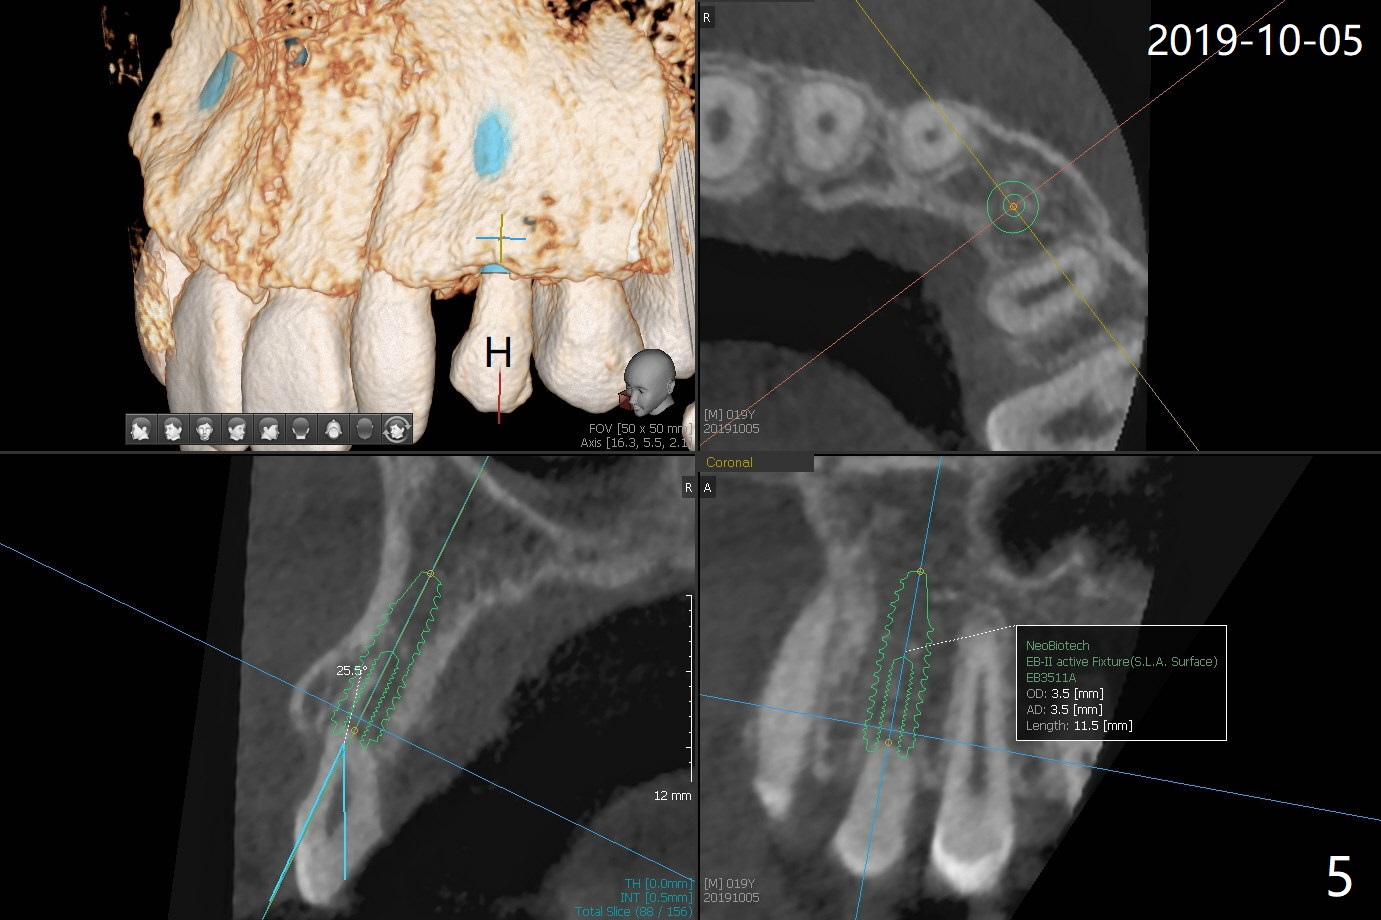

A 20-year-old man requests implant for the loose upper left deciduous canine. Pre-orthodontic panoramus shows 3 implants are needed (Fig.1). Post-ortho PAs indicate root resorption of the upper right deciduous canine as well (Fig.2,3). To reduce radiation, 5x5 cm CBCT is taken for the anterior maxilla, the 1st implant to be placed at #11 in the Thanksgiving this year, while the 2nd one at #6 early next January (Fig.4,5). 1-piece implants may simplify treatment.